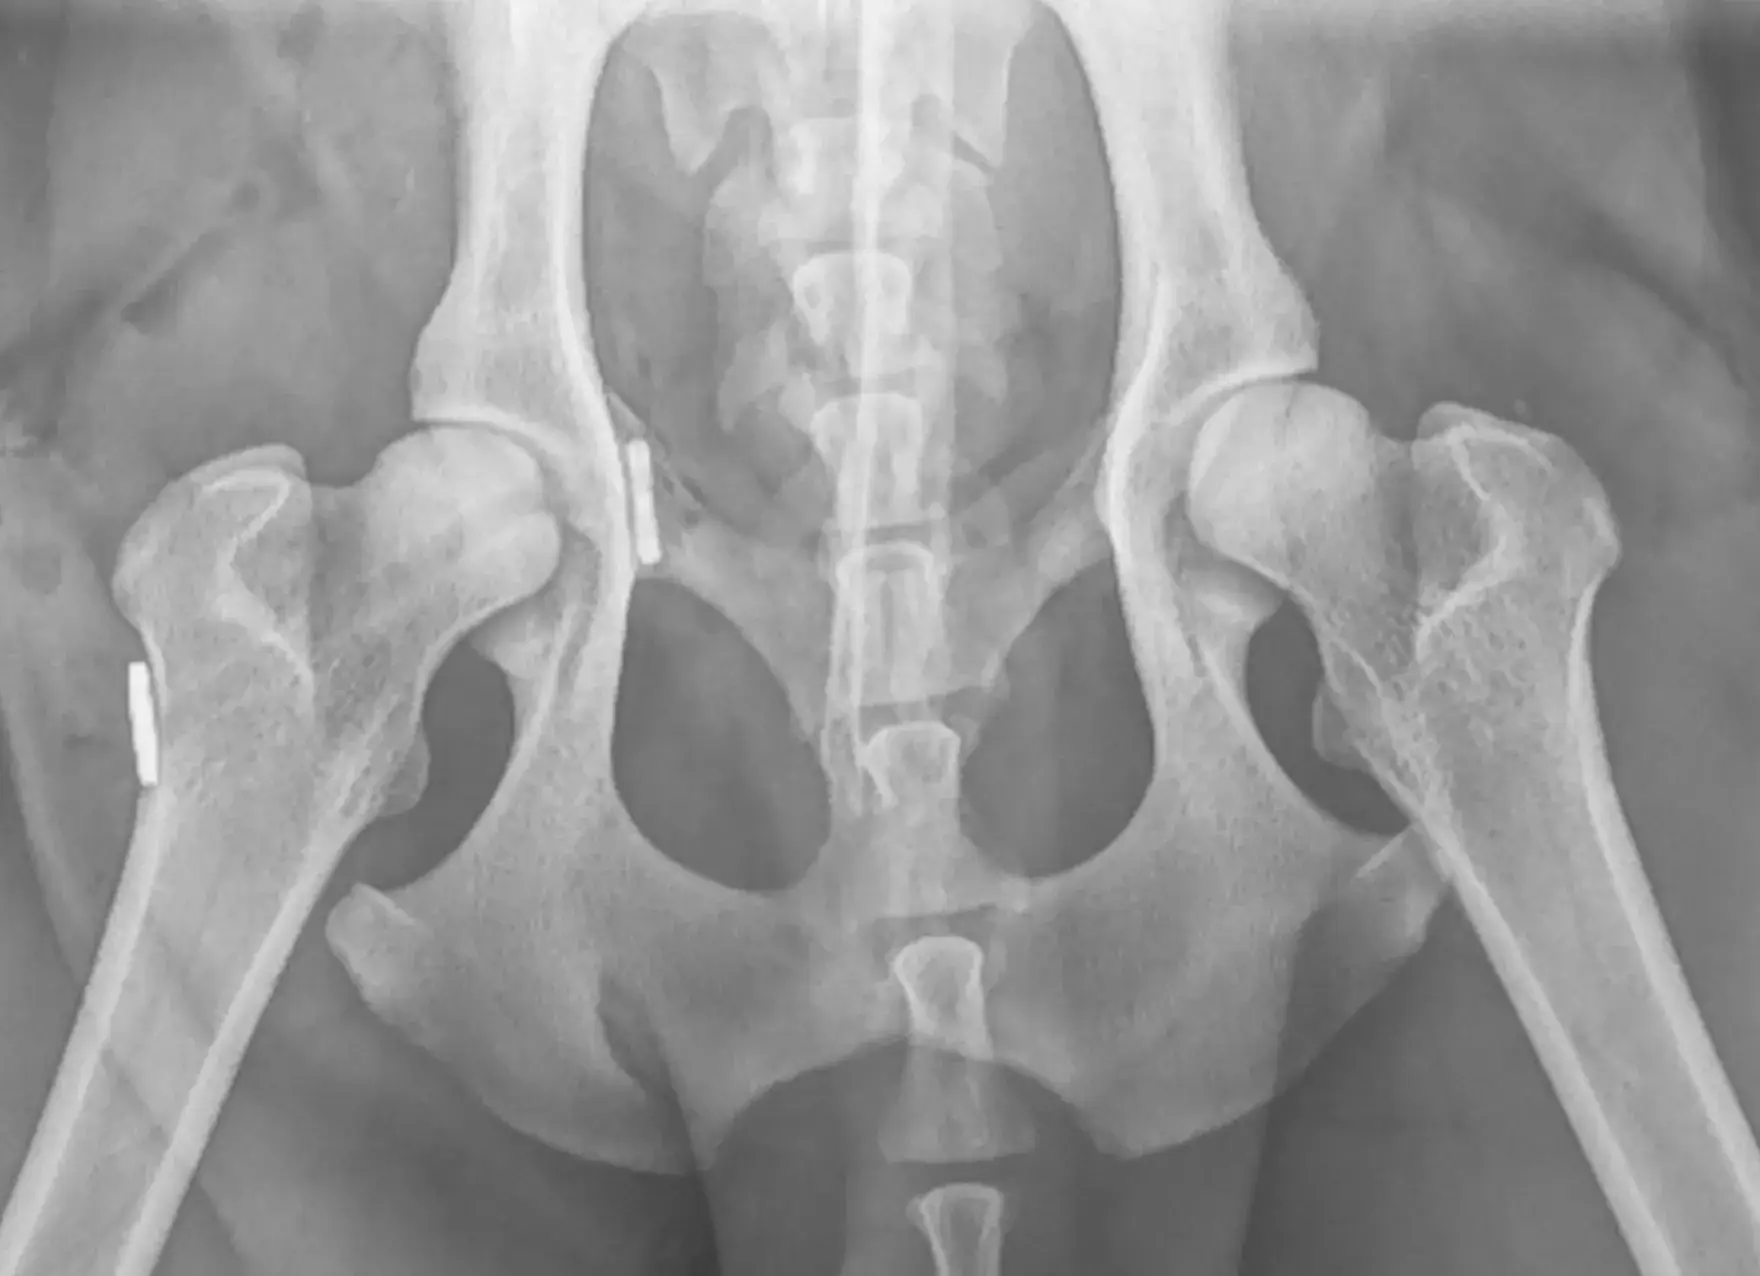

- Dysplasie de hanches